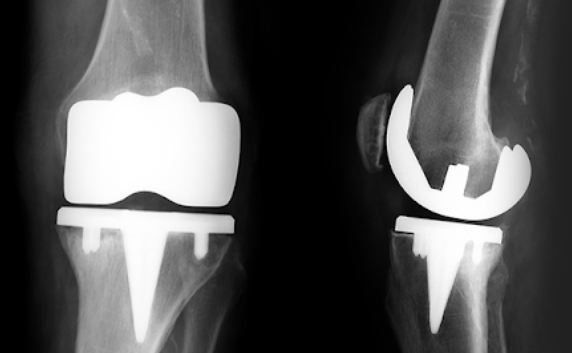

1. 무릎 인공관절 수술이란?

무릎 인공관절 수술은 퇴행성 관절염이나 관절 손상으로 인해 정상적인 생활이 어려운 분들을 위해 손상된 관절을 금속 또는 플라스틱 인공관절로 치환하는 수술입니다.

- 일반적으로 치환술이라고도 하며, 전치환(전체 교체)과 부분 치환술로 나뉩니다.